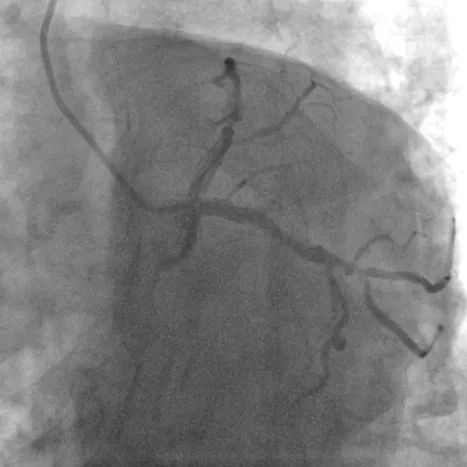

造影:

造影可见,LAD中段狭窄90%,伴有弥漫钙化影,LCX中段次全闭塞,RCA中段60%狭窄,决定先行处理左冠。面对钙化弥漫病变,该病例又将采取什么样的手术方案呢?